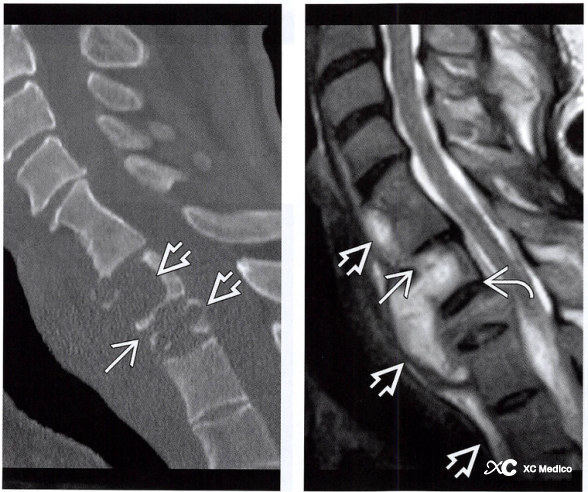

Типичными проявлениями NS являются фрагменты кости, межпозвоночные неровности суставов и несоответствия, приводящие к проскальзыванию тела позвонков, множественным конечным пластинкам и небольшим эрозиям сустава, а также к сохранению плотности кости при склерозе, а также массах мягких тканей.

Примечание: 58-летний мужчина с невропатическим позвоночником. (а) Сагиттальные и (б) корональные компьютерные томографические реконструкции показывают множественные конечные пластины поясничного позвонка и эрозии суставных синовиальных суставов (стрелки) с фрагментами кости. Разрушение блока межпозвоночного диска L2-L3 с расширением межпозвонкового пространства (звездочка). (C) Сагиттальные и (D) осевые T2-взвешенные магнитно-резонансные последовательности, подтверждающие расширение межпозвоночного пространства L2-L3. Значительные изменения пораженного спинного мозга сзади к L2-L3-L4. Существует также выпот в мягких тканях сзади и спереди к остистым процессам (звездочки).